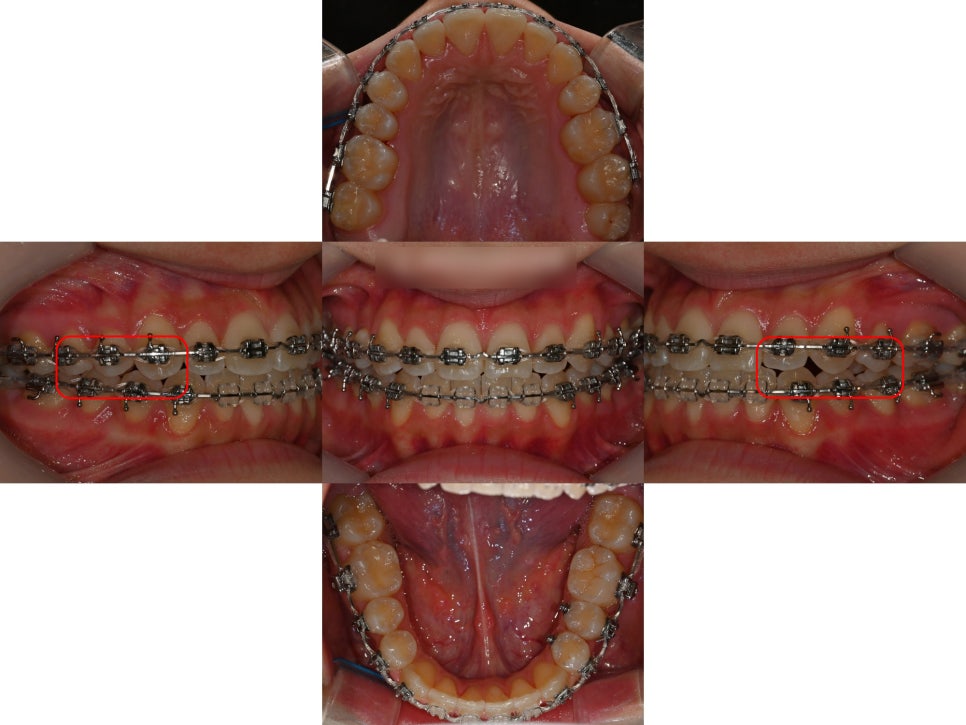

위아래턱의 폭경 부조화를 빠르게 캐치하고

급속구개확장장치(RPE)를 잘 활용한 덕분에

교합을 안정적으로 변화시켜줄 수 있었고,

심하게 틀어져 있던 정중선까지

최대한 맞춰드렸습니다.

가장 중요한 양쪽 어금니 교합이

잘 물리는 상태로 양호하게

마무리 된 모습입니다.